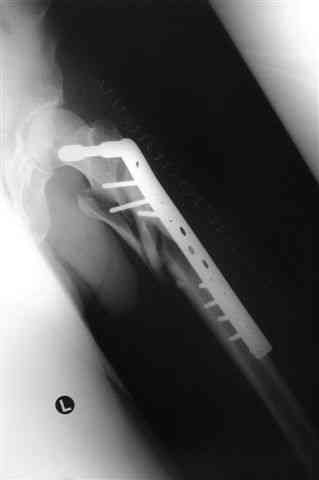

Бедро фиксировал длинной DCS.

По типу бриджинг плэйтин, крюком удалось низвести малый вертел и фиксировать винтом для восстановления медиальной стенки.

В приложении отправляю послеопер. снимки бедра и лодыжки обсуждаемого вчера больного.

В приложении послеоперационные картинки.